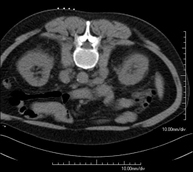

- Abdominal and pelvic CT

Diagnostic test that consists of obtaining high-definition anatomical images (bone structures, vascular structures, liver, pancreas, gallbladder, kidneys, adrenal glands, spleen, small and large intestine, bladder, uterus and ovaries, prostate and seminal vesicles, ureters, etc.) using CT (computed tomography) equipment. Most studies require the use of iodinated contrast.